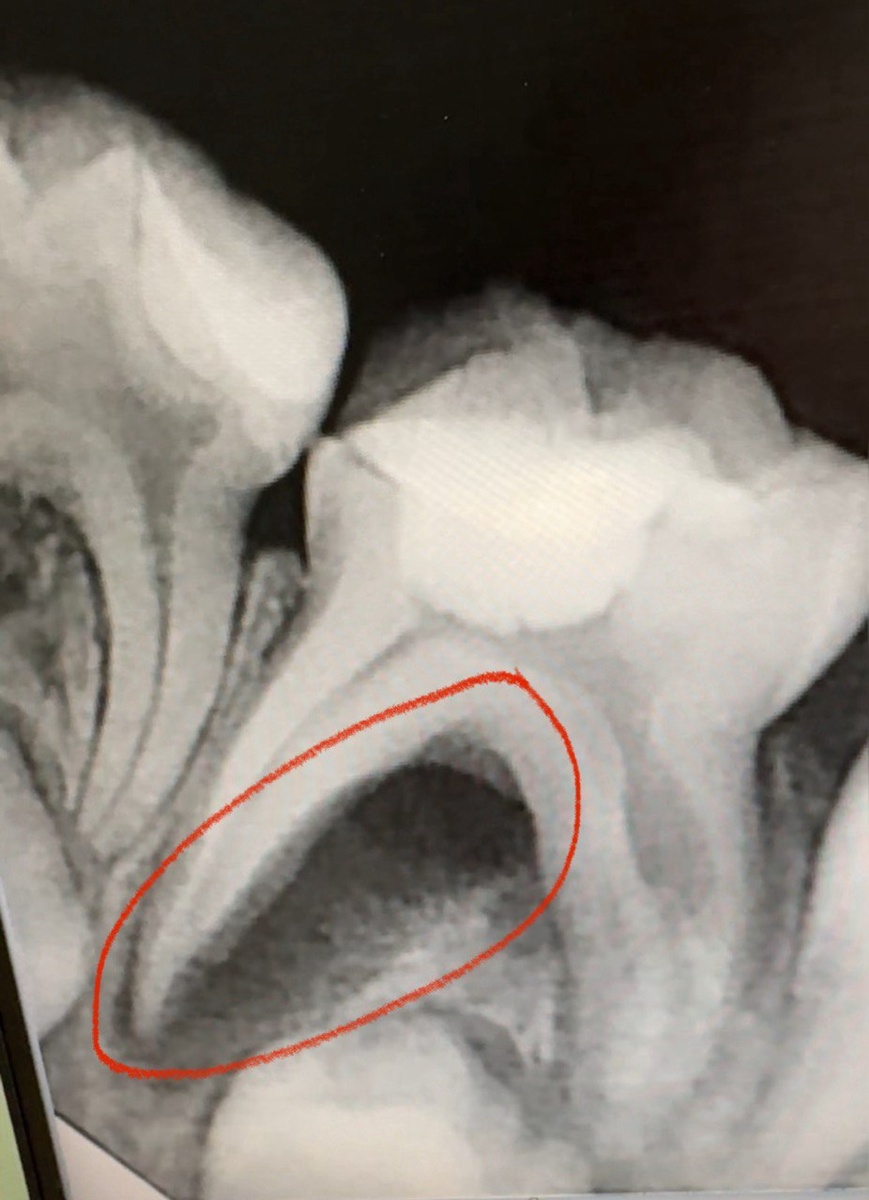

2. На третьем фото в одном из корневых каналов видна внутриканальная резорбция.

И 1 и 2 - это показание к удалению зуба. И конечно, эти изменения не могли произойти за 2 недели, на это нужно гораздо больше времени.